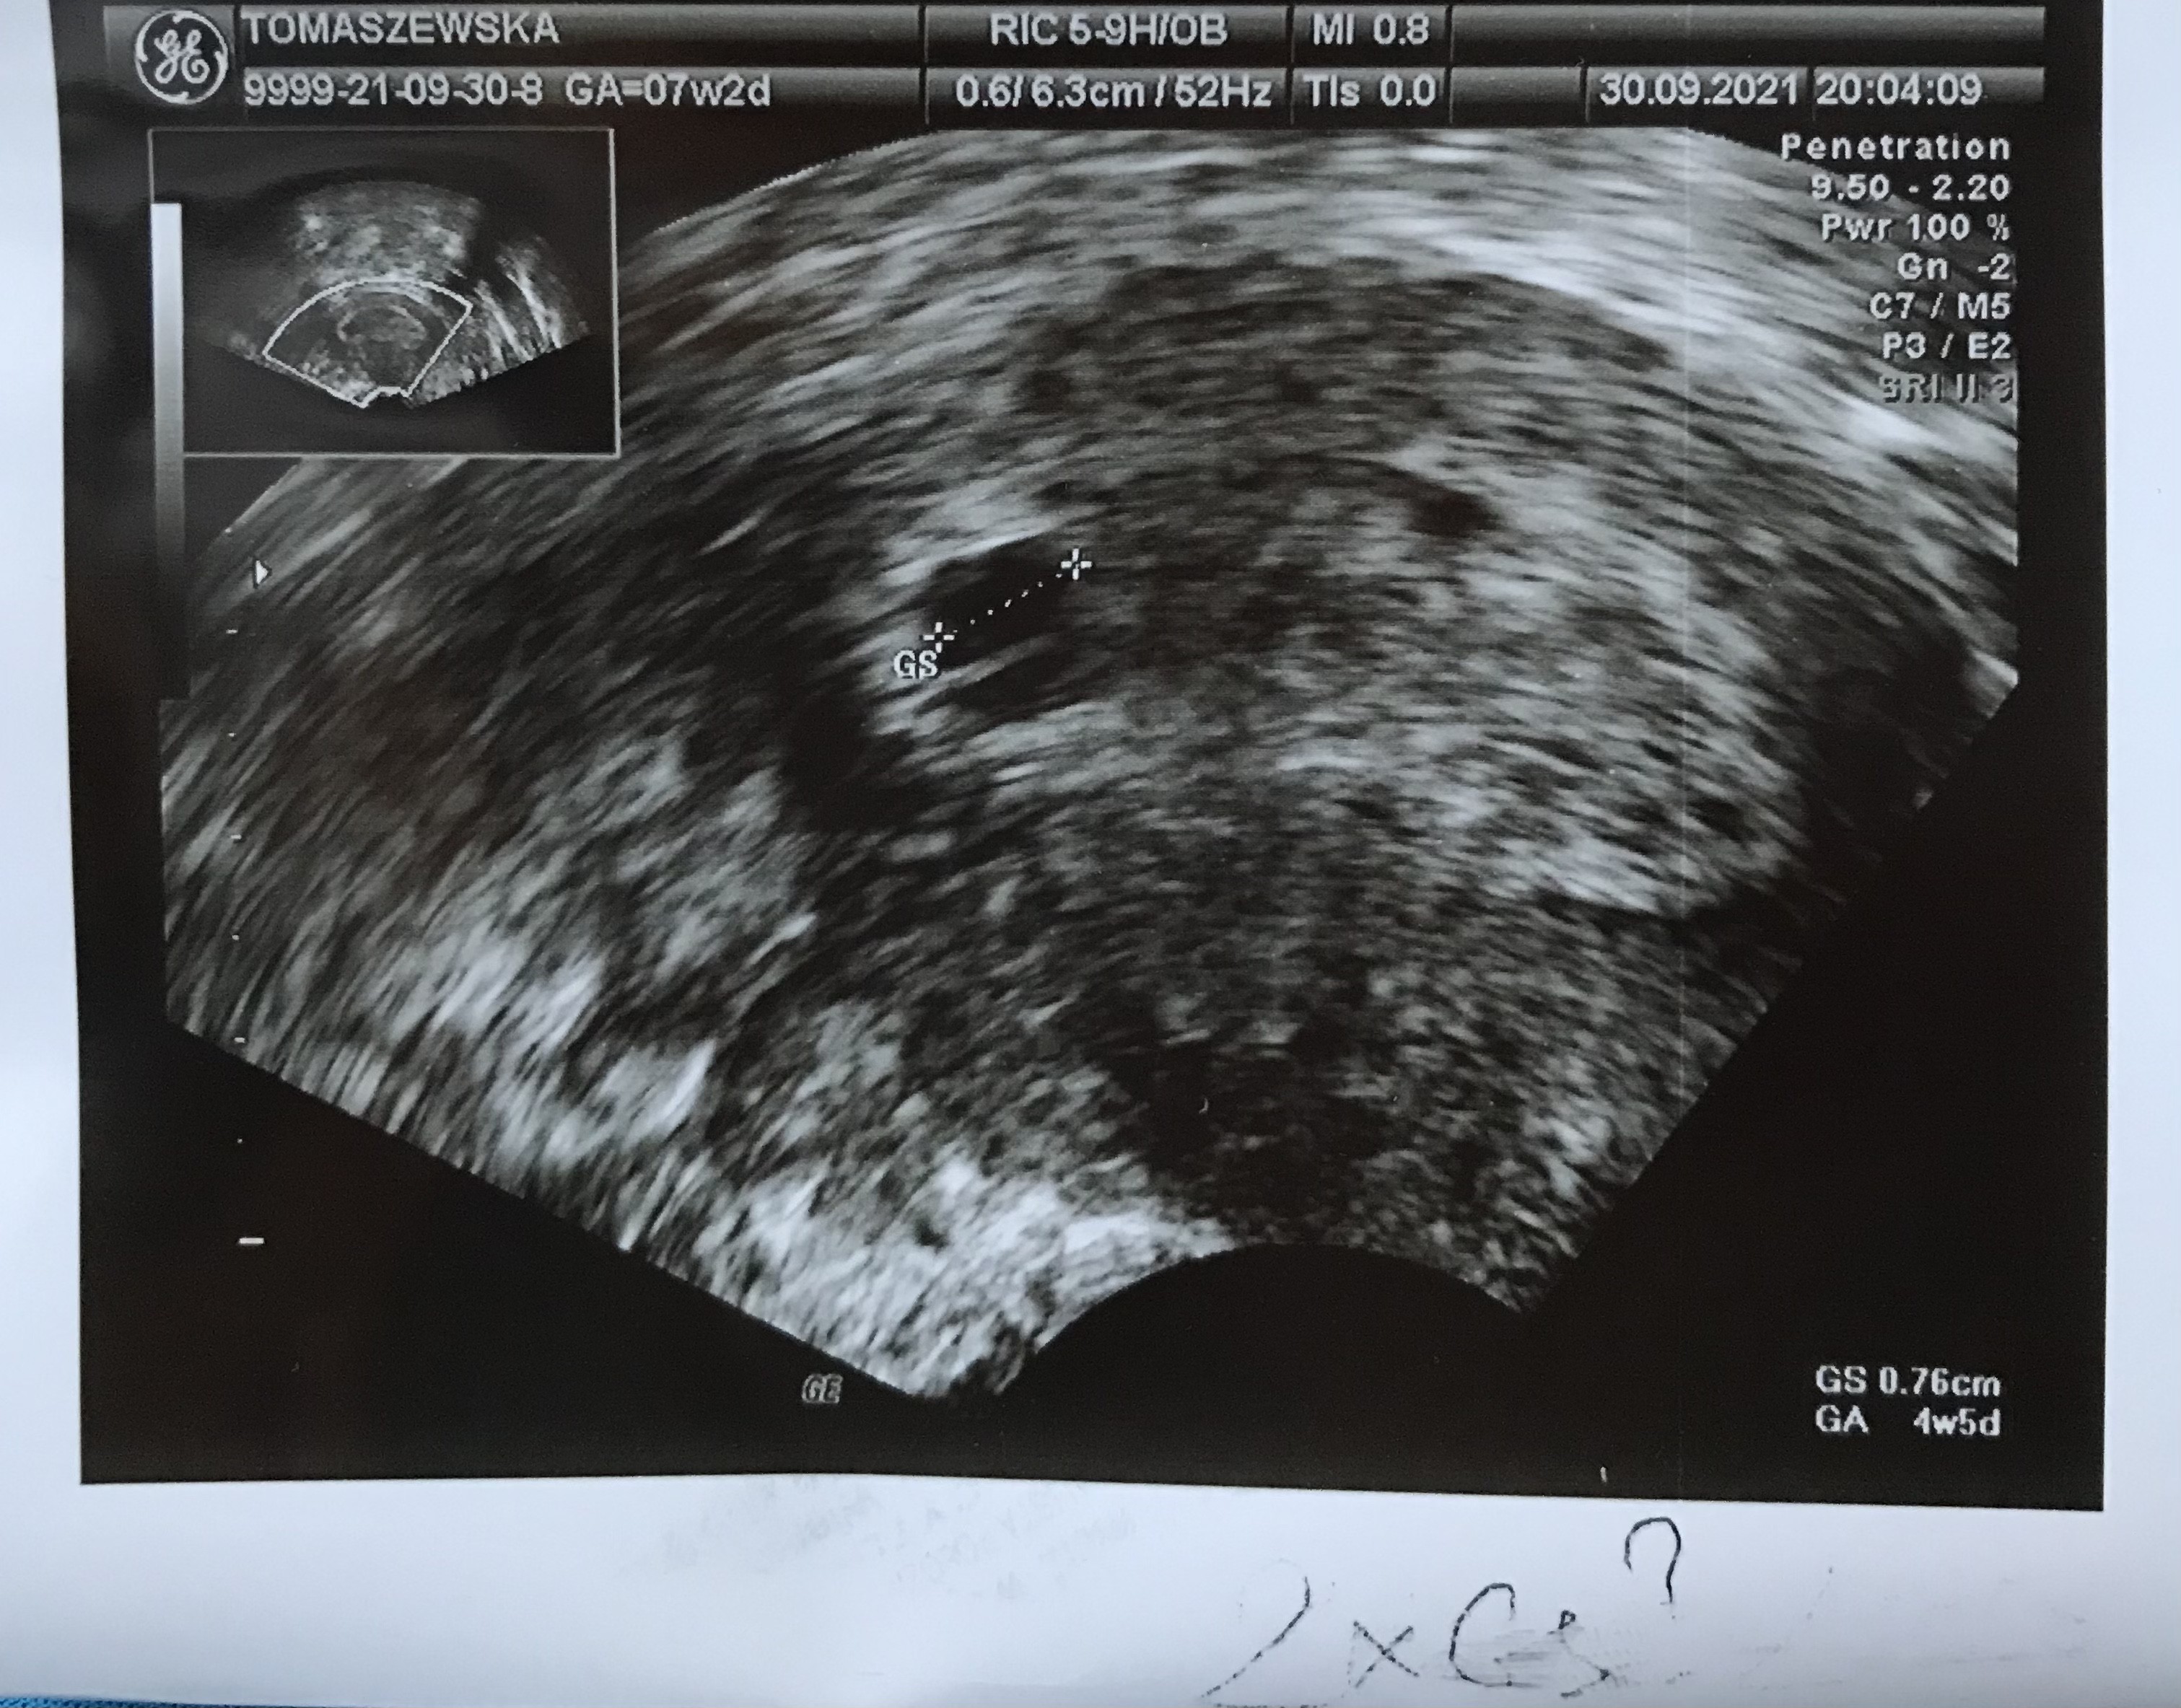

Wczoraj w końcu odnaleźli pęcherzyk - jest młodszy o 2,5 tygodnia 🙈

Jest tez podejrzenie ciąży bliźniaczej

Co myślicie mamy bliźniaków ?

Nie wiem skąd przypuszczenie bliźniaków, skoro nawet 1 zarodka tu nie widać :( Może ten cień pod pęcherzykiem mógłby być drugim pęcherzykiem.

Zarodka nie ma bo za wcześnie , ale lekarz mówił ze w pęcherzyku jest przegroda co może rokować bliźniacza ciąże , chociaż mówił tez ze losy mogą być różne , może zniknąć a może nie. Za 7 dni mam się pokazać